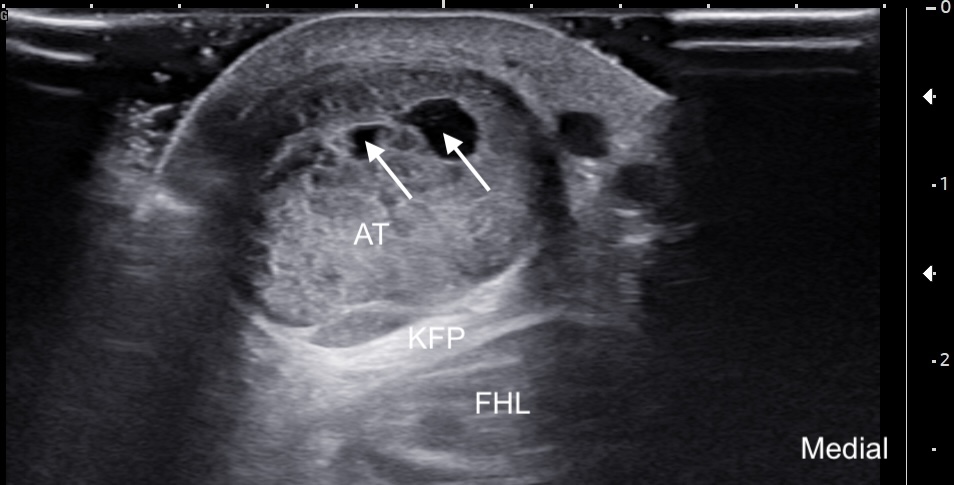

Labeled short-axis ultrasound image of the midportion Achilles tendon showing increased thickness, hypoechogenicity, and a few intrasubstance partial tears. Labels: AT: Achilles tendon, FHL: flexor hallucis longus, KFP: Kager's fat pad, solid arrows: intrasubstance tears